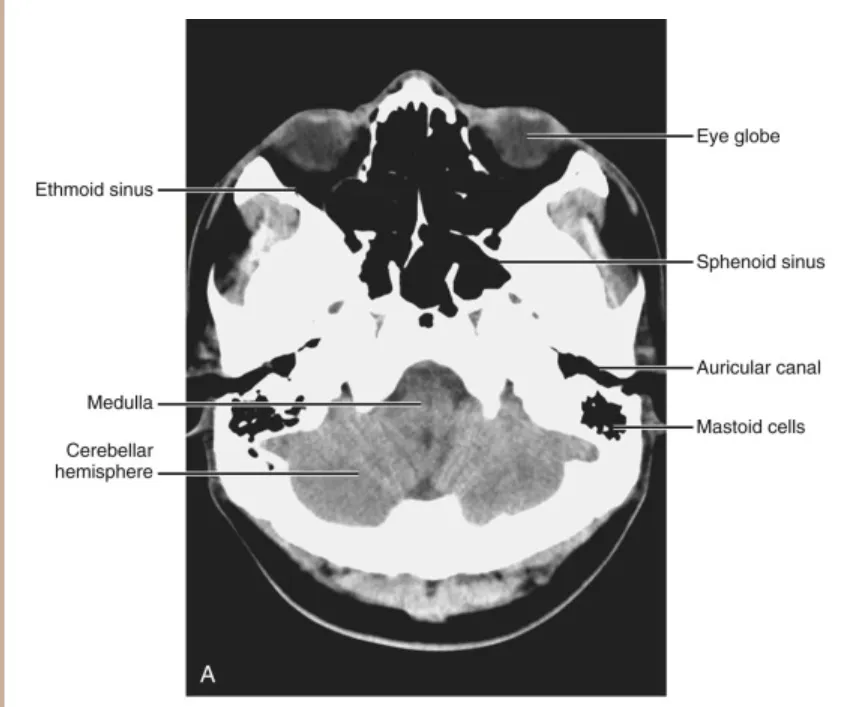

C1. Infratentorial Sections

(1) Below the fourth ventricle

이 단면에서 전두개와(anterior fossa)와 중두개와(middle fossa)의 대부분 구조물은 두개저(skull base)와 안와(orbits)의 구성요소입니다. 중두개와에서 난원공(foramen ovale)과 극공(foramen spinosum)을 CT 스캔의 넓은 윈도우 설정으로 확인할 수 있습니다. 이 구멍들을 통해 각각 삼차신경(fifth cranial nerve)의 세 번째 분지와 중경막동맥(middle meningeal artery)이 지나갑니다. 소뇌반구(cerebellar hemispheres)는 연수(medulla)의 측면에서 볼 수 있습니다. MRI 검사에서는 뇌신경 IX와 X가 이 수준에서 확인될 수 있는데, 이들이 후올리브고랑(postolivary sulcus)에서 나오기 때문입니다. 소뇌반구의 후방 부분은 대조(cisterna magna)의 하부에 의해 윤곽이 그려집니다.